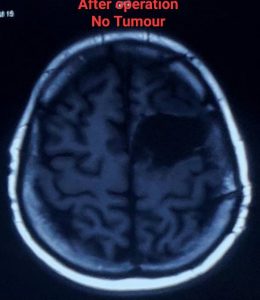

লো-গ্রেড গ্লিওমা (Low-Grade Glioma - LGG)

* সর্বাধিক সম্ভব টিউমার অপসারণ (Maximal Safe Resection): নিউরোসার্জনরা যতটা সম্ভব টিউমারের অংশ অপসারণ করার চেষ্টা করেন, যাতে মস্তিষ্কের গুরুত্বপূর্ণ কার্যকারিতার (যেমন – কথা বলা, নড়াচড়া, স্মৃতিশক্তি) ক্ষতি না হয়। কিছু ক্ষেত্রে, সম্পূর্ণ টিউমার অপসারণ সম্ভব না হলেও, আংশিক অপসারণও রোগের অগ্রগতি ধীর করতে এবং লক্ষণগুলি কমাতে সাহায্য করতে পারে।

সার্জারির পরের যত্ন ও সুস্থতা (Recovery):

সার্জারির পর কয়েকদিন থেকে এক সপ্তাহ হাসপাতালে থাকতে হতে পারে। সুস্থতার প্রক্রিয়া ব্যক্তিভেদে ভিন্ন হতে পারে।

* দীর্ঘমেয়াদী পর্যবেক্ষণ: সার্জারির পরে নিয়মিত এমআরআই স্ক্যান এবং ফলো-আপের প্রয়োজন হয়, যাতে টিউমারের পুনরাবৃত্তি বা উচ্চ-গ্রেডে পরিবর্তনের লক্ষণ দেখা গেলে দ্রুত ব্যবস্থা নেওয়া যায়।

লো-গ্রেড গ্লিওমা সার্জারির পর prognosis বেশ ভালো হতে পারে, বিশেষ করে যদি টিউমার সম্পূর্ণ বা বেশিরভাগ অংশ অপসারণ করা যায়। গবেষণায় দেখা গেছে, দ্রুত এবং কার্যকরী সার্জারি জীবনকাল বাড়াতে এবং খিঁচুনি নিয়ন্ত্রণে আনতে সাহায্য করে। যদিও লো-গ্রেড গ্লিওমা সাধারণত ধীর গতিতে বৃদ্ধি পায়, তবুও এটি সময়ের সাথে সাথে উচ্চ-গ্রেডে পরিবর্তিত হতে পারে। তাই নিয়মিত ফলো-আপ এবং প্রয়োজনে অন্যান্য চিকিৎসা,যেমন – রেডিয়েশন থেরাপি বা কেমোথেরাপি, অত্যন্ত গুরুত্বপূর্ণ।